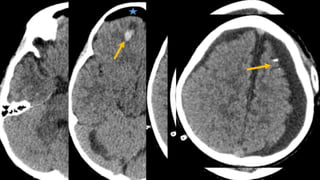

Este documento presenta el caso de un niño de 3 años que sufrió episodios de paresia y alteraciones neurológicas. Exámenes revelaron la presencia de un higroma cerebral que fue drenado. A pesar de una mejoría inicial, el niño continuó presentando síntomas neurológicos intermitentes. Exámenes posteriores identificaron una rara vasculopatía que afecta vasos cerebrales y otros órganos, con un pronóstico grave.